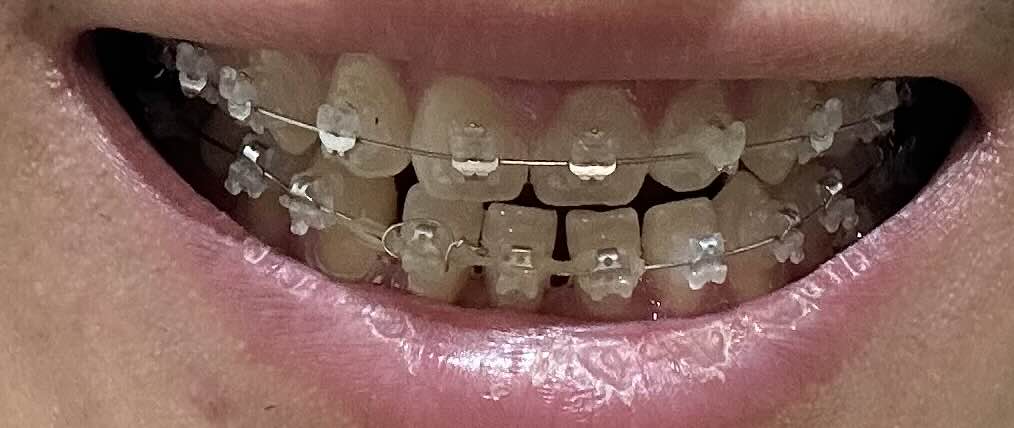

9월 10일 교정 일주일 차

교정 시작한지 일주일 정도가 됐을때 입니다. 정확히는 8일 조금 넘은거 같구요. 엄청 크게 느껴지는 모습은 없지만 확실히 앞니가 조금씩 돌아가는 모습을 볼 수 있습니다. 아직까지 엄청 크게 느껴지지는 않지만 앞니가 벌어진 부분이 조금씩 돌아가는것도 느껴지는거 같구요.